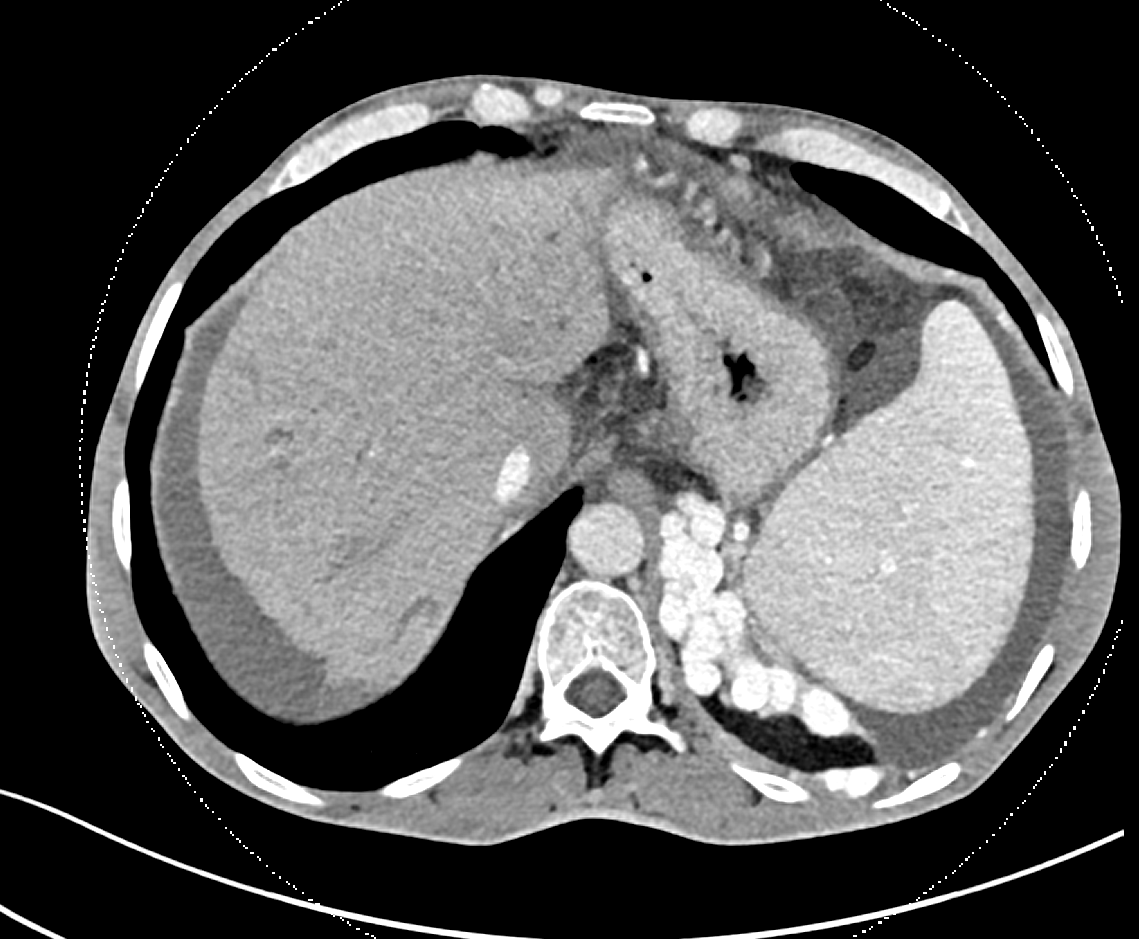

56 Y O known Chronic Liver Disease with Isolated Gastric Varices. Treated by

#Balloon#Occlusion Transvenous#Obliteration and#VascularPlug Placement#Intervention#Radiology#Makkahpic.twitter.com/0eup4cuY7x